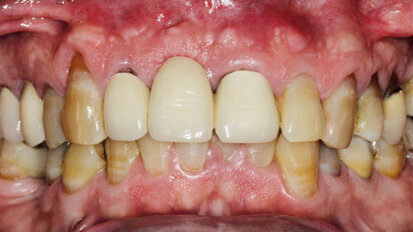

Rehabilitace Straumann